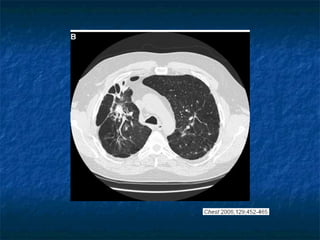

WEGENER´S GRANULOMATOSIS                                Inflamación granulomatosa que involucra el tracto respiratorio, y vasculitis necrotizante que afecta vasos de pequeño y mediano calibre, e.g. capilares, vénulas, arteriolas, y arterias. Glomerulonefritis necrotizante es común.